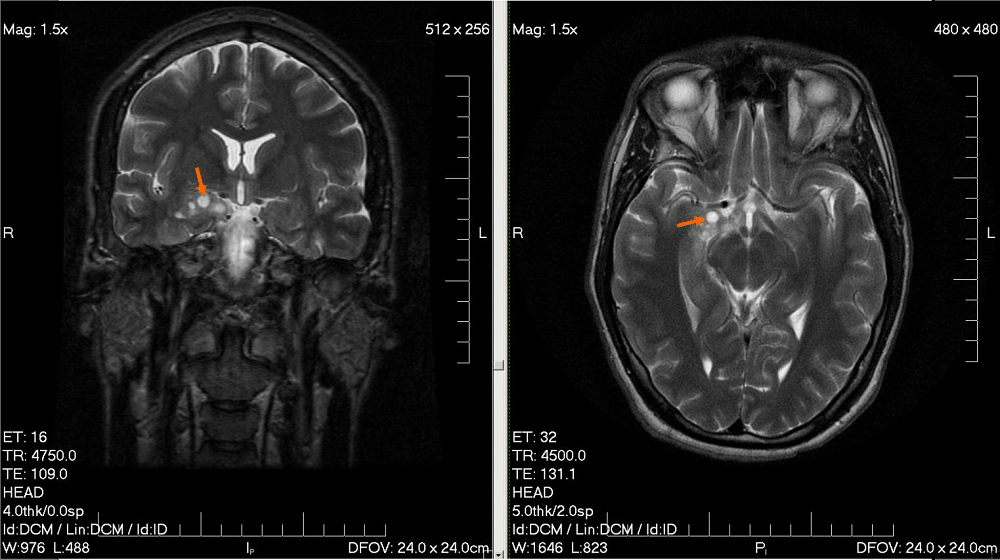

- सीटी स्कैन (CT Scan) या एमआरआई (MRI) से भी ट्यूमर की जांच होती है।